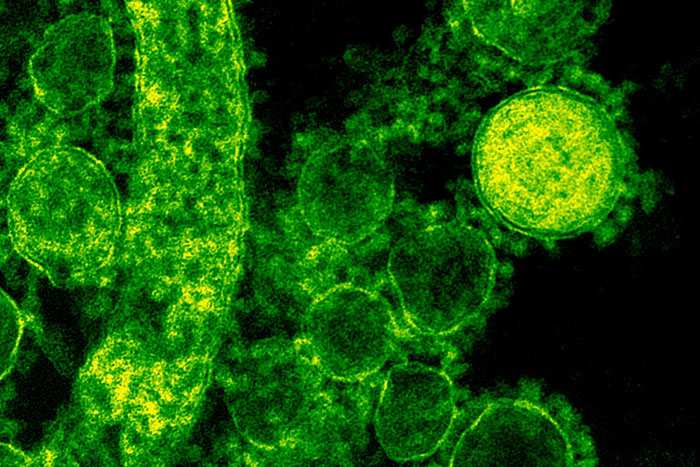

#17

Cold sores can cause inflammation of your brain. It’s called herpetic encephalitis and is likely to cause permanent brain damage even with treatment. It can also be caused by shingles, so getting the shingles vaccine is more important than you think.